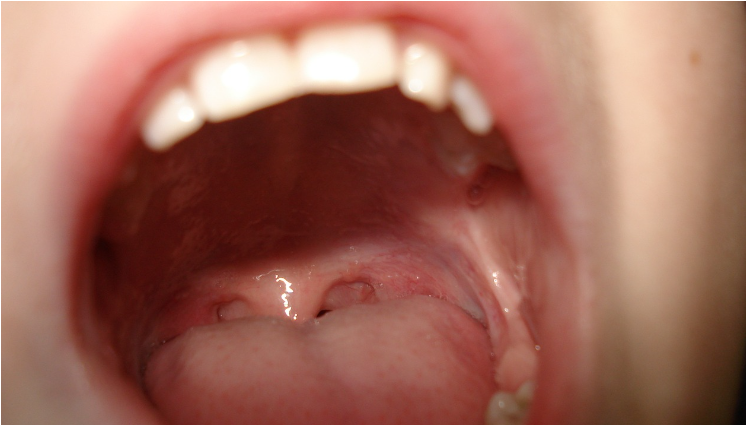

입천장이 붓는 현상은 불편함을 초래하며, 다양한 원인에 의해 발생할 수 있습니다. 이번 포스팅에서는 입천장이 붓는 주요 원인과 이를 치료하는 방법에 대해 알아보겠습니다.

입안의 세균, 바이러스 또는 곰팡이 감염으로 인해 입천장이 부을 수 있습니다. 구강 칸디다증(구강 곰팡이 감염)은 입천장이 붓는 흔한 원인 중 하나입니다.

입천장에 궤양이 생기면 통증과 함께 부종이 발생할 수 있습니다. 구강 궤양은 스트레스, 면역력 저하, 영양 결핍 등의 원인으로 발생할 수 있습니다.